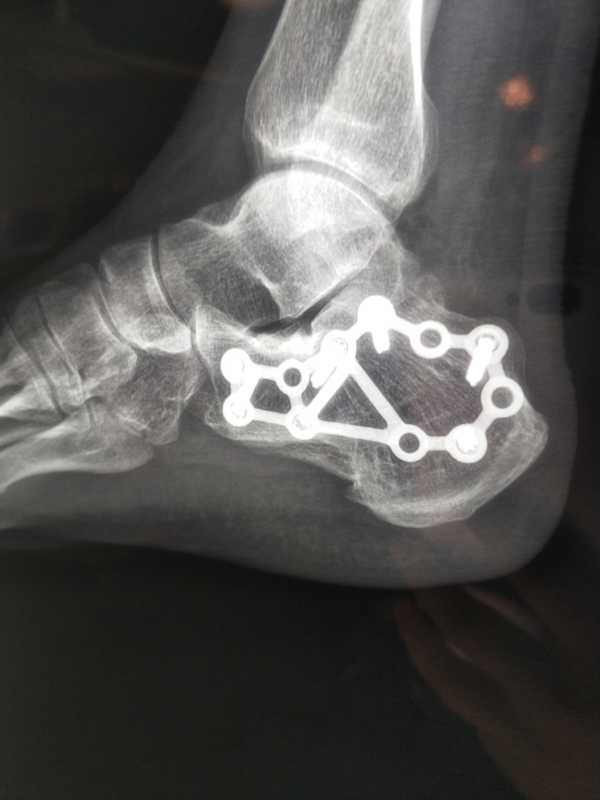

右跟骨图片

右跟骨图片,早上好图片最新图片

左跟骨骨折术后创口不愈合

术后复查dr见跟骨关节面恢复平整!

【一般资料】 男性,44岁,工人 【主诉】 左跟骨骨折1年,行走疼痛加重1

微创治疗跟骨骨折两例

慎独 的想法: 右跟骨骨折取内固定2021.6.22 - 知乎